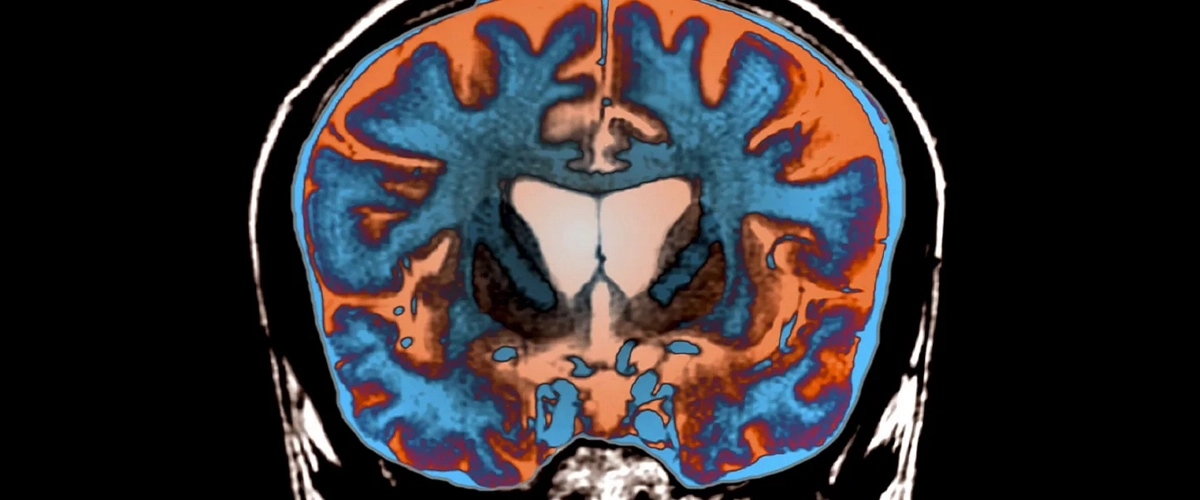

Болезнь Хантингтона: как дефектные белки разрушают ядро нервной клетки

Болезнь Хантингтона — один из самых жестоких генетических приговоров. Мутация в гене HTT заставляет клетки производить дефектный, огромный белок — хантингтин. Он сбивается в комья, копится внутри нейронов и медленно их убивает. Но как именно? Что происходит в эти долгие годы, пока человек теряет контроль над телом и разумом? Ученые давно ломали голову над главной загадкой: почему накопление белка приводит к гибели клетки? Кажется, ответ наконец найден, и он оказался поистине разрушительным.

Исследовательская команда под руководством Гила Корстена и Лукаса Капитейна совершила прорыв. Они обнаружили, что клубки хантингтина не просто «засоряют» клетку — они атакуют самую её суть. Их мишень — ядерная оболочка, прочная мембрана, которая защищает святая святых: нашу ДНК. Представьте крепостную стену, охраняющую королевские архивы. Агрегаты дефектного белка подобно вражеским таранам бьют по этой стене, делая её хрупкой и уязвимой к разрывам.

Как им это удалось разглядеть? Спасибо революционной расширительной микроскопии. Учёные увидели то, что раньше было скрыто: тончайшие фибриллы, торчащие из белковых сгустков, буквально протыкают белковую сеть, укрепляющую оболочку ядра. Это выглядело как медленное, методичное вбивание клиньев. И самое страшное — клетка после такого вторжения теряет способность к ремонту. Разрушенная защита уже не восстанавливается.

«Это может быть общим механизмом для целой группы нейродегенеративных болезней», — отмечает Капитейн. Боковой амиотрофический склероз, некоторые формы деменции — возможно, во всех этих случаях токсичные белки выбирают одну и ту же слабую точку: ядерную оболочку. Один пролом в этой защите запускает катастрофическую цепную реакцию: хаос с генами, сбои в работе нейрона, его смерть и, как следствие, воспаление, которое губит соседние клетки. По сути, учёные нашли то самое первое падающее костяшку домино в страшном каскаде разрушений.